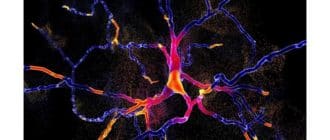

パーキンソン病およびレビー小体型認知症は、いずれも、神経死に関連する障害のある脳機能を特徴とする。画期的な新しい研究では、ニューロン損傷の背後にある主な原因 – アルファ – シヌクレインタンパク […]